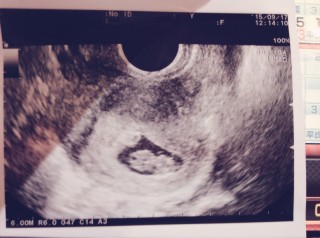

8w0dです。 前回は8w6dで稽留流産でした。 茶おりが出て心配で慌てて受診。 赤ちゃんの心拍は元気で大きさも標準と言われました! 茶おりの原因は子宮の入口に小さいポリープがあってそれが原因だろうと言うことでした。 今取ってしまうと流産や早産の可能性があるから、しばらく様子を見ましょうという事に。 とにかく赤ちゃんが元気で一安心でした。

一週間ぶりの検診。 エコー写してる時間が短くて心拍は見れなかったけど、前回の6ミリから1cmまで大きくなっていました。 前回は見えなかった卵黄嚢もハッキリ見えて、赤ちゃんもよーく見ると目のようなものが見えて感動。 排卵日から計算すると8w0dですが、胎芽の大きさから7w3dと言われました。 母子手帳の説明は二週間後です。 でも、分娩の病院の予約をすぐ取り一安心です。 二週間後、どれくらい大きくなっているか楽しみです。